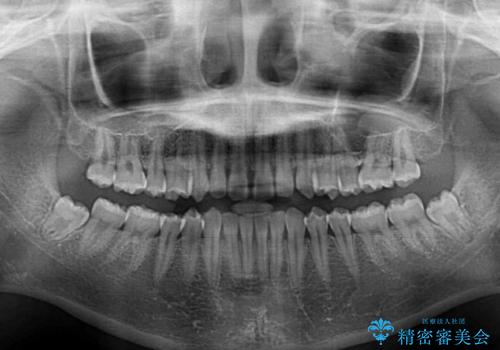

- 上顎前歯の隙間を気にして来院された患者様です。

目立たない装置を希望とのことで、インビザラインを用いて矯正治療を行うこととしました。

一度インビザラインのマウスピースセットをお渡しすると1年以上来院されず、マウスピースを破損したり紛失したりすると来院されるというのんびりとしたペースで治療を行ったため、4年間という長期にわたる治療となりました。

最終的には隙間は全て閉じ、綺麗な仕上がりとなりました。